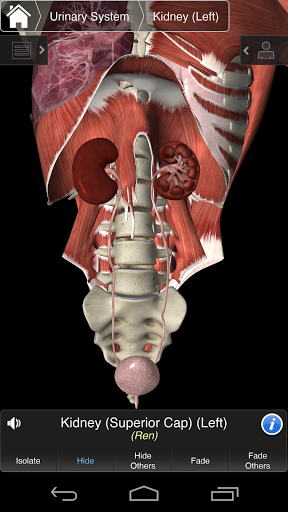

⁃Urinaire

Essential Anatomy 3 est réactif, visuellement magnifique et sans effort. L'application est entièrement 3D, ce qui signifie que vous pouvez voir n'importe quelle structure anatomique dans l'isolement, ainsi que de n'importe quel angle.

---- Mode de sélection multiple - Masquer / Fondu / Isoler des structures individuelles ou multiples

---- Corriger la prononciation audio pour chaque structure

---- Nomenclature latine pour chaque structure anatomique